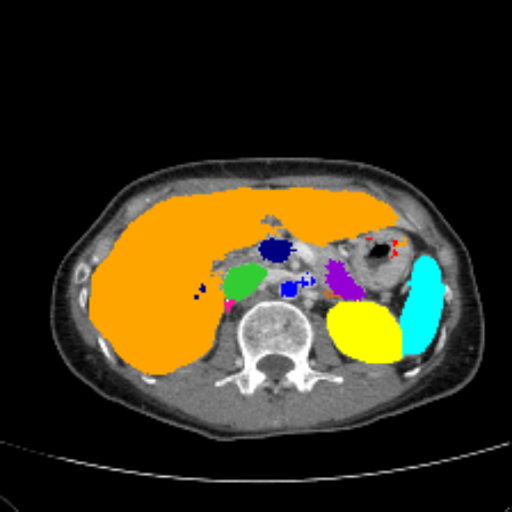

Figure 3 presents a qualitative comparison of segmentation performance on examples from the Synapse, BTCV, ACDC, and ISIC17 datasets. The first two examples (from Synapse) highlight variations in segmentation performance among U-Net, TransUnet, Mamba-Unet, and Swin-Unet. While Swin-Unet performs well in the first example, its performance decreases in the second example, particularly in segmenting the organ highlighted in blue. Additionally, it misclassifies background regions as the class highlighted in orange. In contrast, our approach demonstrates high robustness in segmenting all classes accurately and aligning well with the ground truth masks.

Across BTCV, ACDC, and ISIC17, the comparison methods exhibit varying performance depending on the task and class. For instance, Mamba-Unet struggles to segment multiple organs in BTCV, even misclassifying certain classes as others. In the ACDC dataset, both TransUnet and Mamba-Unet perform poorly in segmenting the three classes. In the last column (ISIC17), Swin-Unet oversegments the skin lesion compared to the ground truth. Unlike the comparison models, our approach consistently delivers effective segmentation across different tasks and datasets.

These qualitative findings further reinforce the quantitative results presented in the experimental section, demonstrating the effectiveness of our MambaCAFU model in handling binary and multi-class segmentation across diverse medical imaging modalities and tasks.

Slice GT Unet TransUnet Mamba-Unet Swin-UMamba MambaCAFU-V1

Figure 3: Visual comparison of segmentation examples from Synapse (first two examples), BTCV (3-4 examples), ACDC (5th example) and ISIC17 (last example). Columns: input slice, ground truth, Unet, TransUnet, Mamba-Unet, Swin-UMamba, and MambaCAFU-V1.